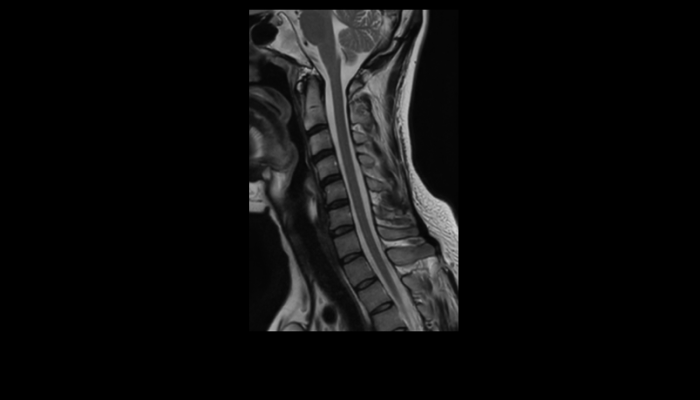

頭部MRI画像 頭部MRI脳腫瘍や脳梗塞、認知症など脳の病気を詳細に評価します。 MRA画像 頭部MRA造影剤を使わずに脳の動脈を描出します。動脈瘤や狭窄を検索します。 脊椎MRI画像 脊椎MRI椎間板ヘルニアや脊柱管狭窄症など脊椎や脊髄の疾患を評価します。 腹部MRI画像 上腹部MRI・MRCP肝臓・胆のう・膵臓・腎臓などの上腹部の重要臓器を詳細に評価します。 乳房MRI画像 乳腺MRIマンモグラフィや超音波と併せて、乳がんを検索や病変の範囲を評価します。 前立腺MRI画像 前立腺MRI前立腺がんを検索します。PSA高値の方はまず前立腺MRIをお勧めします。 子宮・卵巣MRI画像 子宮・卵巣子宮筋腫や子宮体癌、卵巣腫瘍など女性特有の病気を評価します。 膝関節MRI画像 膝関節膝関節の骨や靭帯、半月板を評価します。靭帯断裂や半月板損傷などレントゲンでは評価できない構造も診断できます。 肩関節MRI画像 肩関節肩関節の骨や腱、靭帯を評価します。腱板断裂や腱の断裂などレントゲンでは評価できない構造も診断できます。 心臓MRA 心臓MRA狭心症、心筋梗塞の原因となる冠動脈の狭窄を評価します。造影剤を使用せず、撮影可能です。 DWIBS画像 DWIBS全身のがんを広く検索します。リンパ節や転移の評価にも優れます。